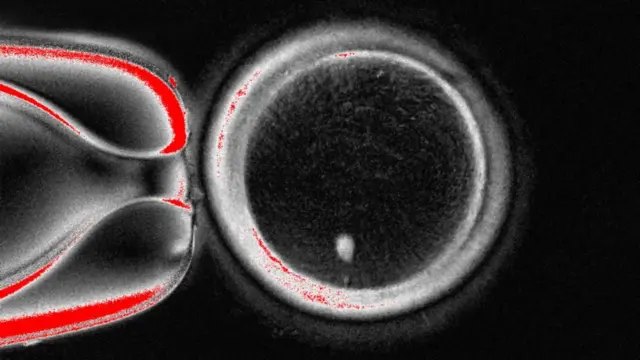

Fuente de la imagen, OHSU/Christine Torres Hicks

Científicos estadounidenses han creado por primera vez embriones humanos en etapas tempranas manipulando ADN extraído de células cutáneas y fecundándolos con esperma.

Con la técnica del equipo de investigación de la Universidad de Salud y Ciencias de Oregón, se extrae el núcleo —que alberga una copia de todo el código genético necesario para construir el cuerpo— de una célula de la piel.

Este se coloca luego dentro de un óvulo de una donante al que se le han quitado las instrucciones genéticas.

Hasta ahora, la técnica es similar a la utilizada para crear a la oveja Dolly, el primer mamífero clonado del mundo, nacida en 1996.

Sin embargo, este óvulo no está listo para ser fecundado por un espermatozoide, ya que contiene un conjunto completo de cromosomas.

Heredas 23 de estos pares de ADN de cada uno de tus progenitores, para un total de 46, que el óvulo ya posee.

Así pues, la siguiente etapa consiste en persuadir al óvulo para que descarte la mitad de sus cromosomas en un proceso que los investigadores han denominado “mitomeiosis” (el término se refiere a la fusión de la mitosis y la meiosis, las dos formas en que las células se dividen).

El estudio, publicado en la revista Nature Communications, mostró que se crearon 82 óvulos funcionales. Estos fueron fecundados con espermatozoides y algunos progresaron hasta las primeras etapas del desarrollo embrionario. Ninguno se desarrolló más allá de los seis días.